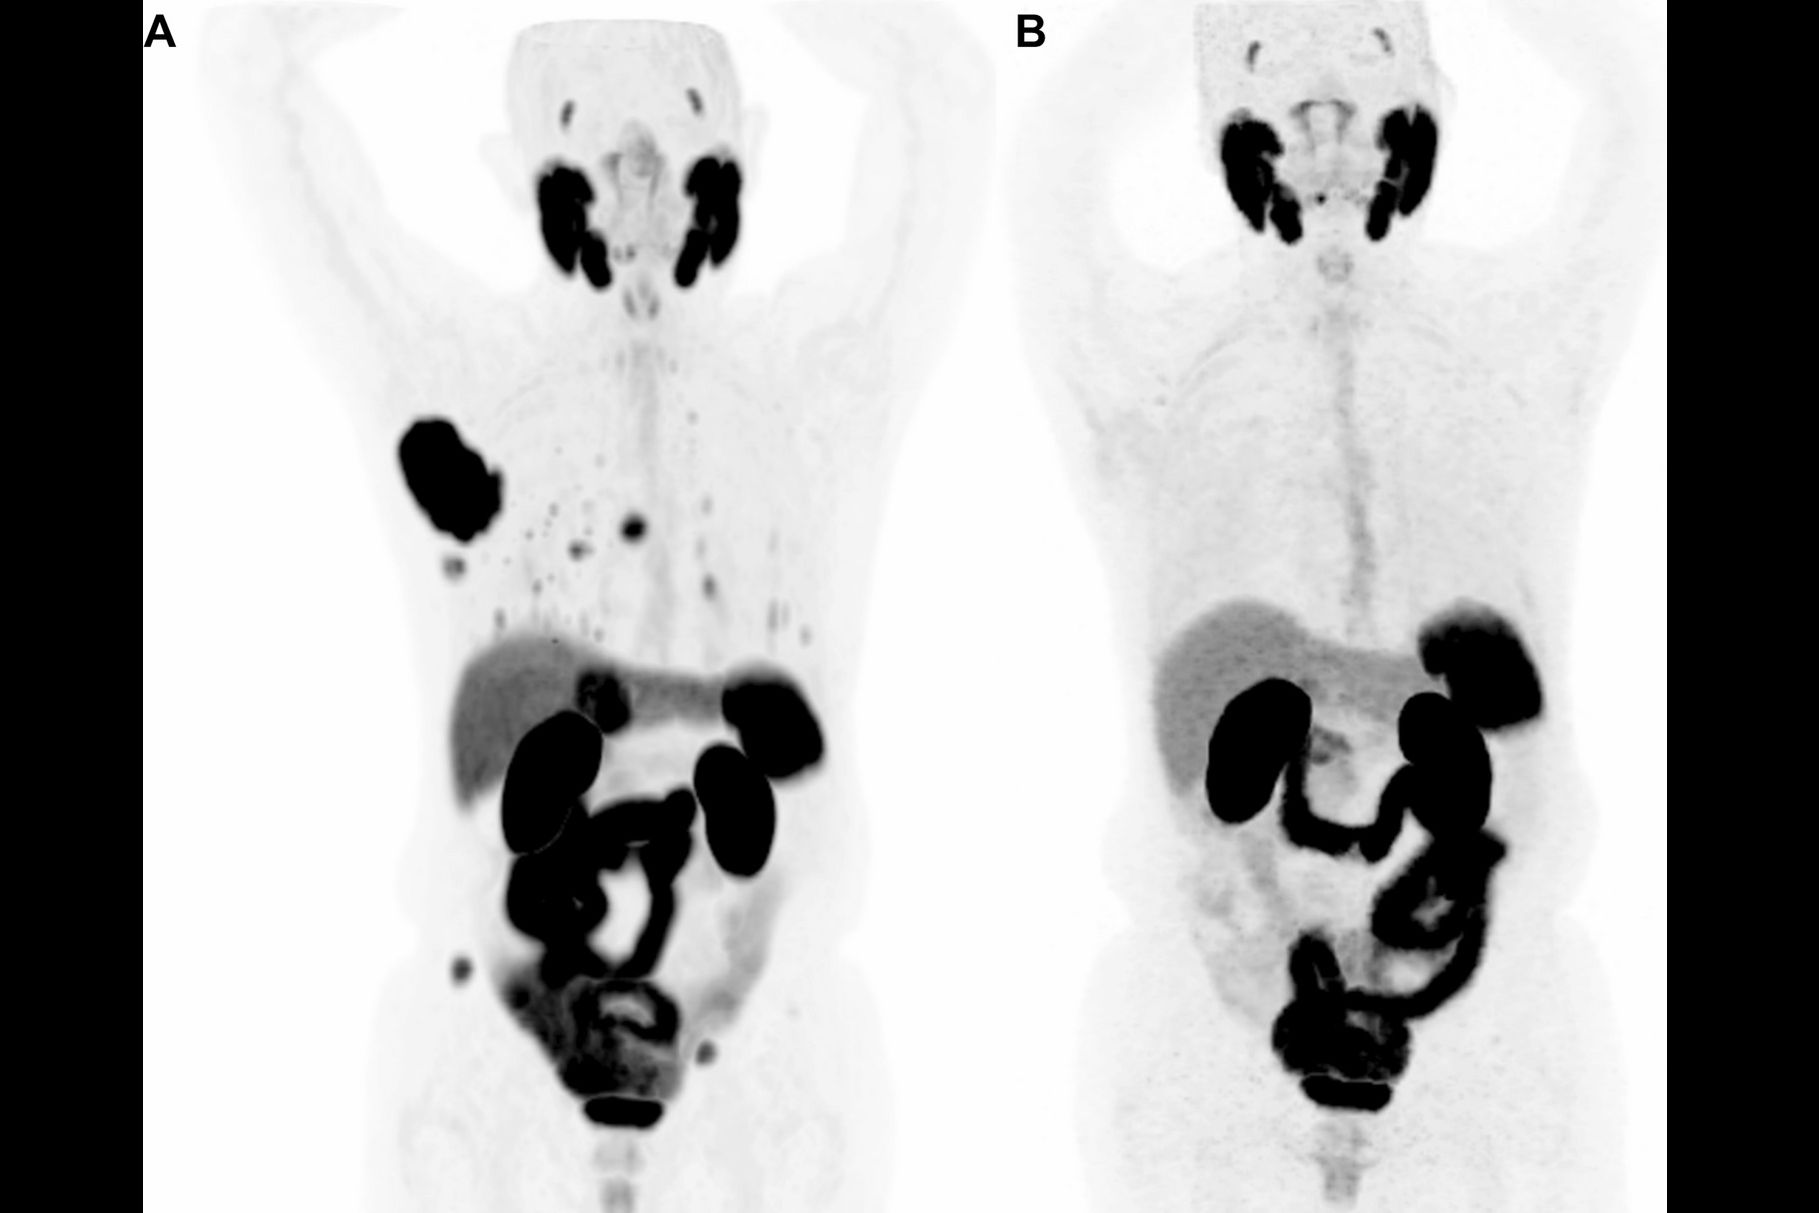

SPECT imaging of Tc-99m MAG3-tofersen in healthy human volunteers. (A) Maximum-intensity-projection images showing distribution of Tc-99m MAG3-tofersen in humans (n = 3) one, four, and 24 hours after intrathecal injection. Time–activity curves derived from SPECT data measuring activity in ROIs in CNS (lumbar, thoracic, and cervical spine ROIs include both cord and proximal CSF) (B), kidneys and liver (C), and brain atlas (D).Journal of Nuclear Medicine

“The broad uptake of the [tracer] in the brain and spinal cord in the healthy volunteer study is consistent with the clinical effects of tofersen observed in individuals with SOD1-ALS,” the group wrote.